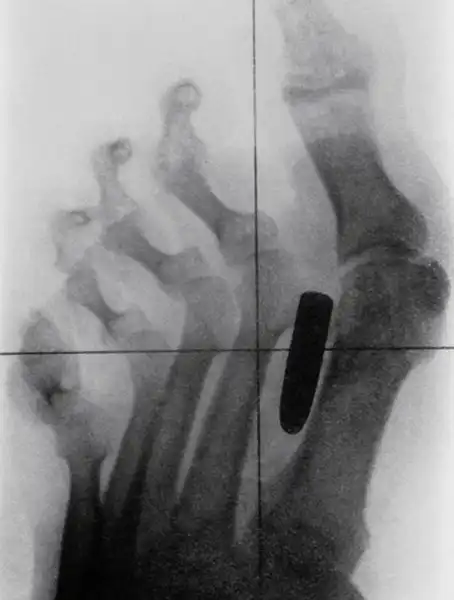

Старинный рентгеновский снимок ступни солдата англо-бурской войны (1899-1902) с огнестрельным ранением. Пуля застряла между большим и вторым пальцами.